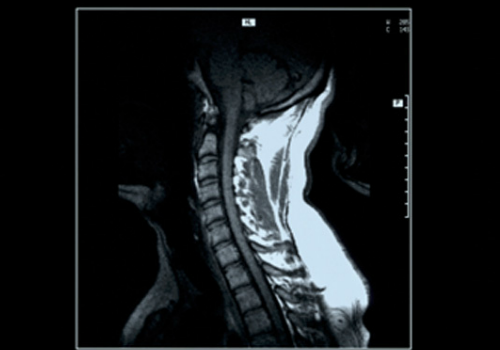

腰痛、肩こり、不眠症の方へ、大阪 睡眠改善研究室のオーダーメイド枕

(*)実際のMRI画像と異なります。

頸椎椎間板ヘルニア等でオーダーメイド枕をお探しの方へ。

睡眠改善研究室では、済生会病院と連携を取り【頸椎ドックMRI】検査をおすすめしています。

手のシビレやめまい等に繋がる頸椎椎間板ヘルニアですが、何か特別な事をしたわけでもなく気付かずになってしまう場合もあるのが特徴です。頸痛や腰痛等は運動療法や姿勢など日常生活上の注意によって緩和することがありますが、椎間板ヘルニアなど脊椎の軟骨が変性し症状を出している場合は原因を見極め正しく対処する事も大切です。

睡眠中は基本的に無意識状態になりますので、睡眠中(主に)頚椎から後頭部にかけての負担を軽減させ、睡眠姿勢を安定させる為にオーダーメイド枕が効果的になりますが、同時に【頚椎ドックMRI】などで椎間板・椎骨そのものの状態を確認するのも、原因対処に効果的になりますので、大阪 睡眠改善研究室では済生会病院と連携をとり検査をお勧めしています。